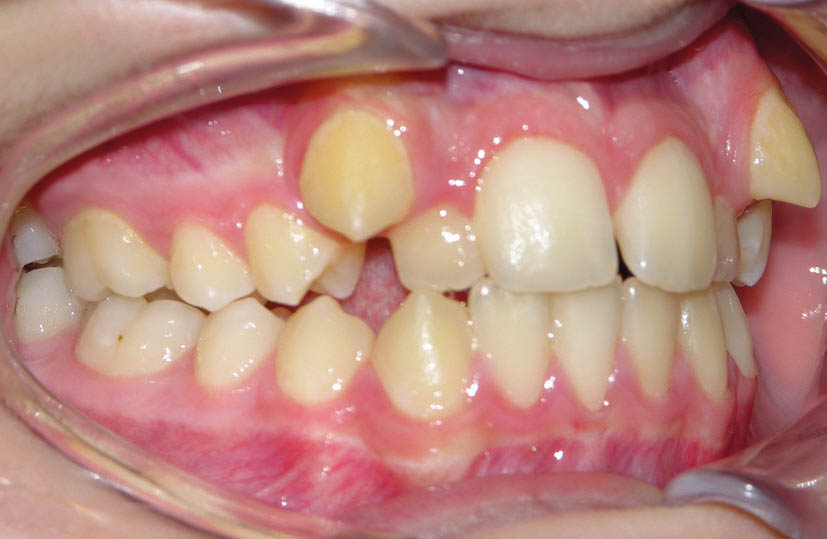

خیلی از مواقع نامرتبی نسبتاً زیادی در بالا میبینید و فکر میکنید که باید پرمولرهای بالا را کشید (شکل 96-2) اما وقتی اکلوژن را میبینید، شاهد یک اورجت صفر و یک رابطه مولری کلاسI هستید و اگر پائین غیرکشیدنی باشد، در این صورت باید دندانهای بالا را پروترود کنید تا در عین حال که مرتب میشوند یک اورجت صحیح هم به شما بدهد پس اینگونه بیماران غیر کشیدنی میشوند (شکل 96-2 الی 99-2).

شکل 98-2: اکلوژن کلاسI در سمت چپ

شکل 99-2: اکلوژن کلاسI در سمت راست